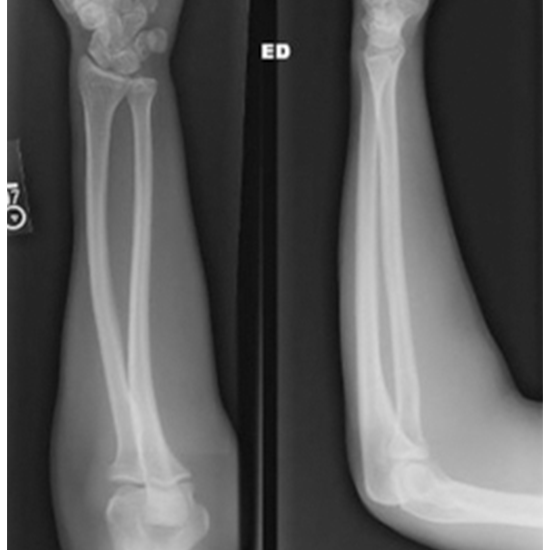

X-ray Left Forearm, Lat View

An X-ray of the forearm can visualize the bones of the forearm and the soft tissues (skin and muscles) surrounding them. The forearm includes the elbow, forearm bones (radius and ulna), and the wrist.